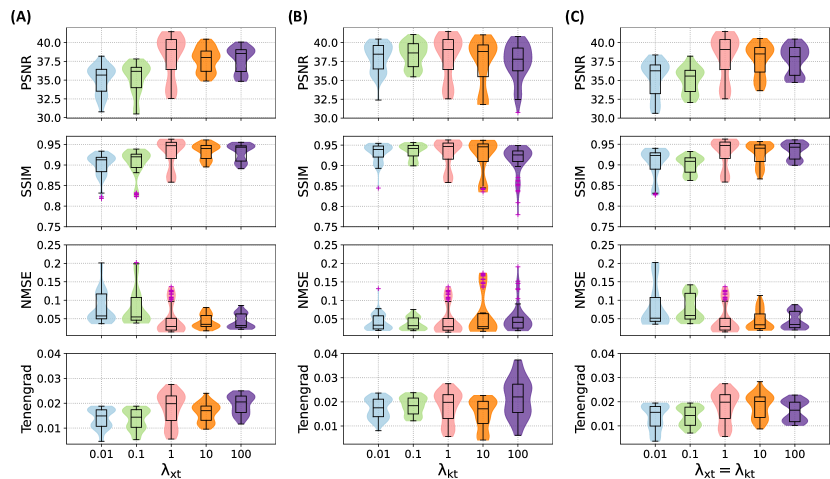

The ablation study evaluated the effectiveness of the proposed temporal guidance priors, including - and - priors, by analyzing results with different weighting factors and from Eq. (22) on cardiac cine data, as presented in Supporting Information Figure S3. The influence of the number of reverse diffusion steps on reconstruction fidelity and computational runtime was analyzed on cardiac cine data, as depicted in Supporting Information Figure S4. Additionally, the impact of incorporating the CG module during inference was assessed on dynamic lung data, with results shown in Supporting Information Figure S5.

Incorporating - and - regularization—derived directly from time-resolved data provides valuable guidance during the diffusion process. This approach ensures accurate temporal alignment and enhances the recovery of fine image details, as is shown by comparing dDiMo with other competitive methods with (e.g., CRNN) or without (e.g., DiMo) temporal characterization. Also, it was highlighted in the ablation study results (Supporting Information Figure S3) that the reconstruction performance of the - prior improves significantly as its weighting factor increases, with optimal results achieved at . A similar trend is observed for the - prior, with the performance increasing when the weighting factors increase to 1. This illustrates the contribution of - and - regularization to improving reconstruction performance in the cardiac cine data. However, notably, the performance wasn’t further improved with a higher - and - weight, indicating optimal performance exists with dataset-specific tunning of those numbers. While not shown in the result, we realized the result for the golden-angle radial lung data relies more on the - component rather than the - characterization, as we used a relatively small weight 0.001 for - component. This is mainly because the learning of the accurate - priors in the center ACS region of radial k-space is extremely challenging and prone to error due to the highly oversampled k-space center and small ACS coverage, especially at extremely few radial spokes (e.g., 35 or 17 spokes at Figure 7) [63]. The CG layer also plays an important role in enhancing performance within this framework. Supporting Information Figure S4 illustrates that while dDiMo without CG can recover a substantial amount of image structure from undersampled data, it often results in less clear images. By implementing temporal sparsity through CG optimization, sharper reconstructions with finer details are achieved as the weighting factor in Eq. (20) increases. In the lung dataset, the optimal value for was found to be 0.015. Higher values led to degraded reconstructions, which were characterized by noise and blurring. Nevertheless, we demonstrate the inclusion of - and - priors and CG into the diffusion modeling can be beneficial to characterize dynamic information in dynamic MRI reconstruction; care has to be cast to carefully leverage the good aspects of those modules. As with many dedicated deep learning algorithms with fine structures and components, hyperparameter tuning is never trivial and forgiven, including for dDiMo. Further research is warranted to explore robust, cost-effective, and hopefully automatic ways to facilitate this process [64].

Figure S3. Results of the ablation study for cine cardiac MR image reconstruction at 4 acceleration using dDiMo, demonstrating the impact of the weighting factors and on the loss function, with the noise estimation loss fixed at 1. Violin plots summarize reconstruction performance under the following conditions: (A) Varying values while is fixed at 1. (B) Varying values while is fixed at 1. (C) Both and set to equal, varying values. These experiments evaluate the relative contributions of - and - priors to the reconstruction of cine short-axis (SAX) and long-axis (LAX) cardiac MR images. For the experiments presented in the manuscript, and were both set to 1, achieving an optimal trade-off between noise estimation, - prior, and - prior learning, resulting in high reconstruction quality and efficiency.